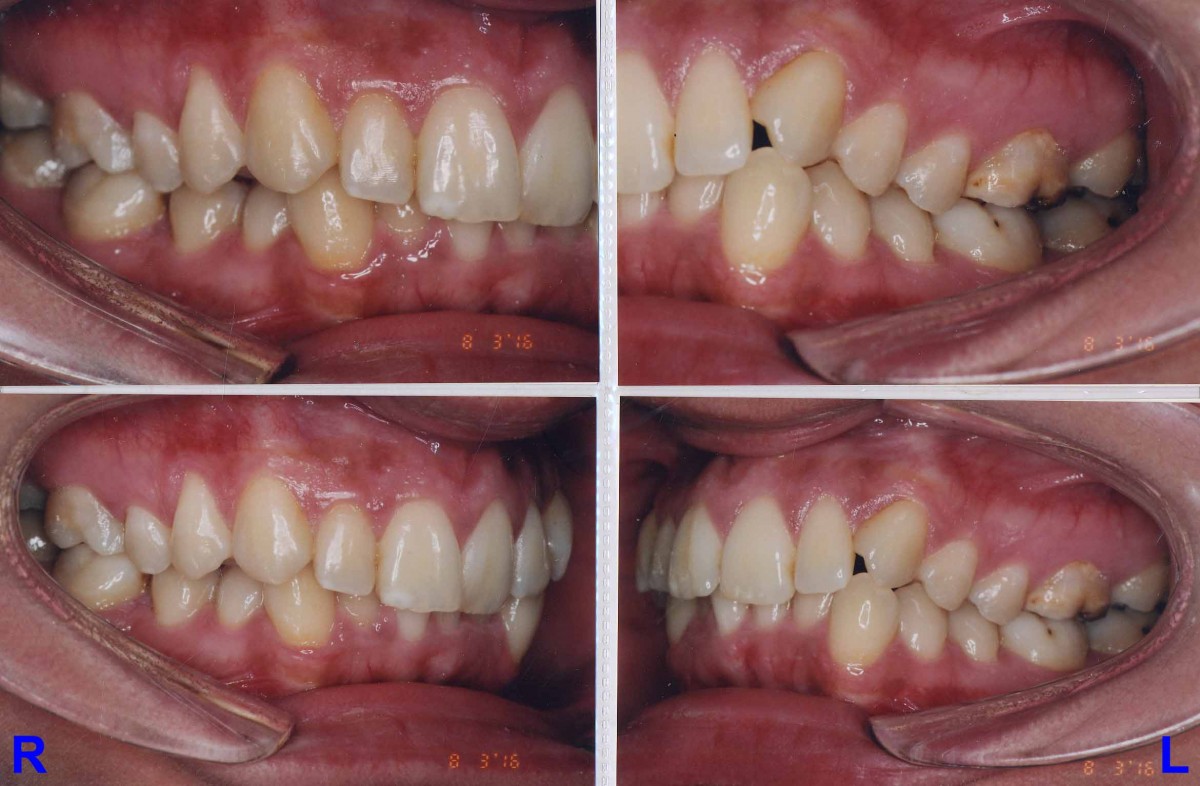

Pacient 23 ani. Extracție 1.4, 2.4, 3.5, 4.5, aparat ortodontic fix ceramic.